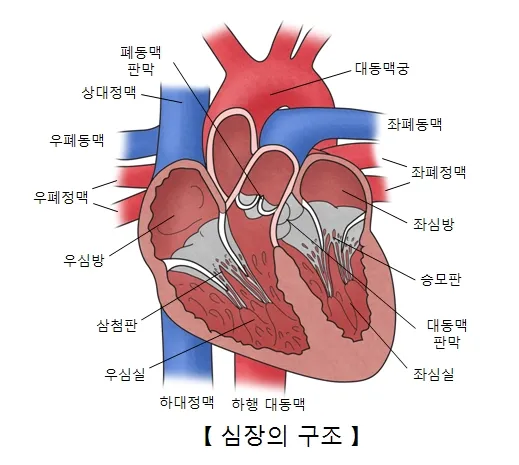

1. 심장 관련 원인

- 부정맥: 정상 심박수 범위 60-100회/분 이탈

- 심장 판막 이상: 증상 발현 시 심박수 변동 20% 이상

- 빈맥증: 휴식 시에도 심박수 100회/분 이상

- 서맥증: 심박수 60회/분 이하로 저하